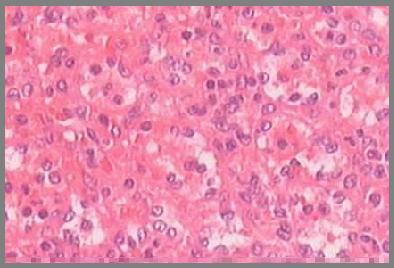

肺炎性假瘤是肺内良性肿块,是由肺内慢性炎症产生的肉芽肿、机化、纤维结缔组织增生及相关的继发病变形成的肿块,并非真正肿瘤。肺炎性假瘤较常见。